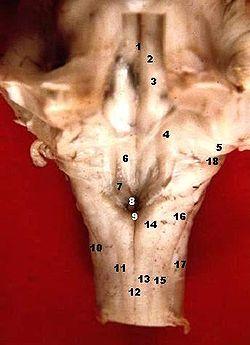

Human caudal brainstem posterior view description.JPG

Human caudal brainstem posterior view (Dorsal cochlear nucleus is #5)